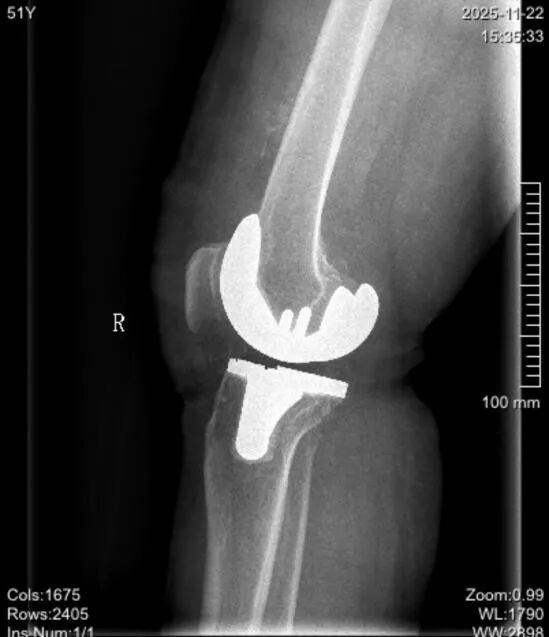

接受手术的5位患者均被诊断为重度膝关节骨性关节炎,且病情复杂多样,涵盖了严重内翻畸形、屈曲挛缩、外翻畸形及伴有骨质缺损等具有代表性的复杂病例,采用传统TKA手术挑战较大。

▲术前术后影像对比

▲影像对比

术前,手术团队根据患者CT影像数据进行三维建模与虚拟手术规划,精确设定“仿生内轴膝”假体的型号、安放位置、角度及截骨量,并前瞻性地在虚拟空间中模拟了截骨后的软组织平衡状态。术中,在鸿鹄®机器人的实时导航与视觉引导下,郭洪章主任操控轻量化灵巧机械臂,为不同畸形的患者执行了“量体裁衣”式的精准截骨。实时数据显示,鸿鹄®机器人在纠正严重内外翻力线、平衡屈曲与伸直间隙等关键步骤上,展现出超越传统工具和人眼判断的超高精度与稳定性,确保了“仿生内轴膝”假体所追求的内轴稳定性与生理运动学特性得以完美实现,助力恢复患者膝关节的自然运动功能。术后,患者均感觉良好,疼痛感可控,并于当日在康复团队指导下进行早期功能锻炼,展现了精准手术驱动下的快速康复优势。

郭洪章主任指出,单日高效完成5台复杂的机器人辅助下全膝关节置换手术,实现“量”与“质”的双重飞跃。在流畅的操作与团队娴熟的配合下,从切皮到完成假体安装,单台手术核心步骤仅需约36分钟,其效率已与传统手术相当,但团队工作强度显著下降,患者术中出血、截骨精准度显著上升。这意味着,在鸿鹄®机器人辅助下,手术团队即便面对复杂畸形,也能够高效地将“仿生内轴膝”这一先进假体的设计理念,通过数字化手段精准、可重复地转化为手术现实,真正实现了精准与效率的完美统一,这将为患者的快速康复和长远功能改善提供临床优选方案。